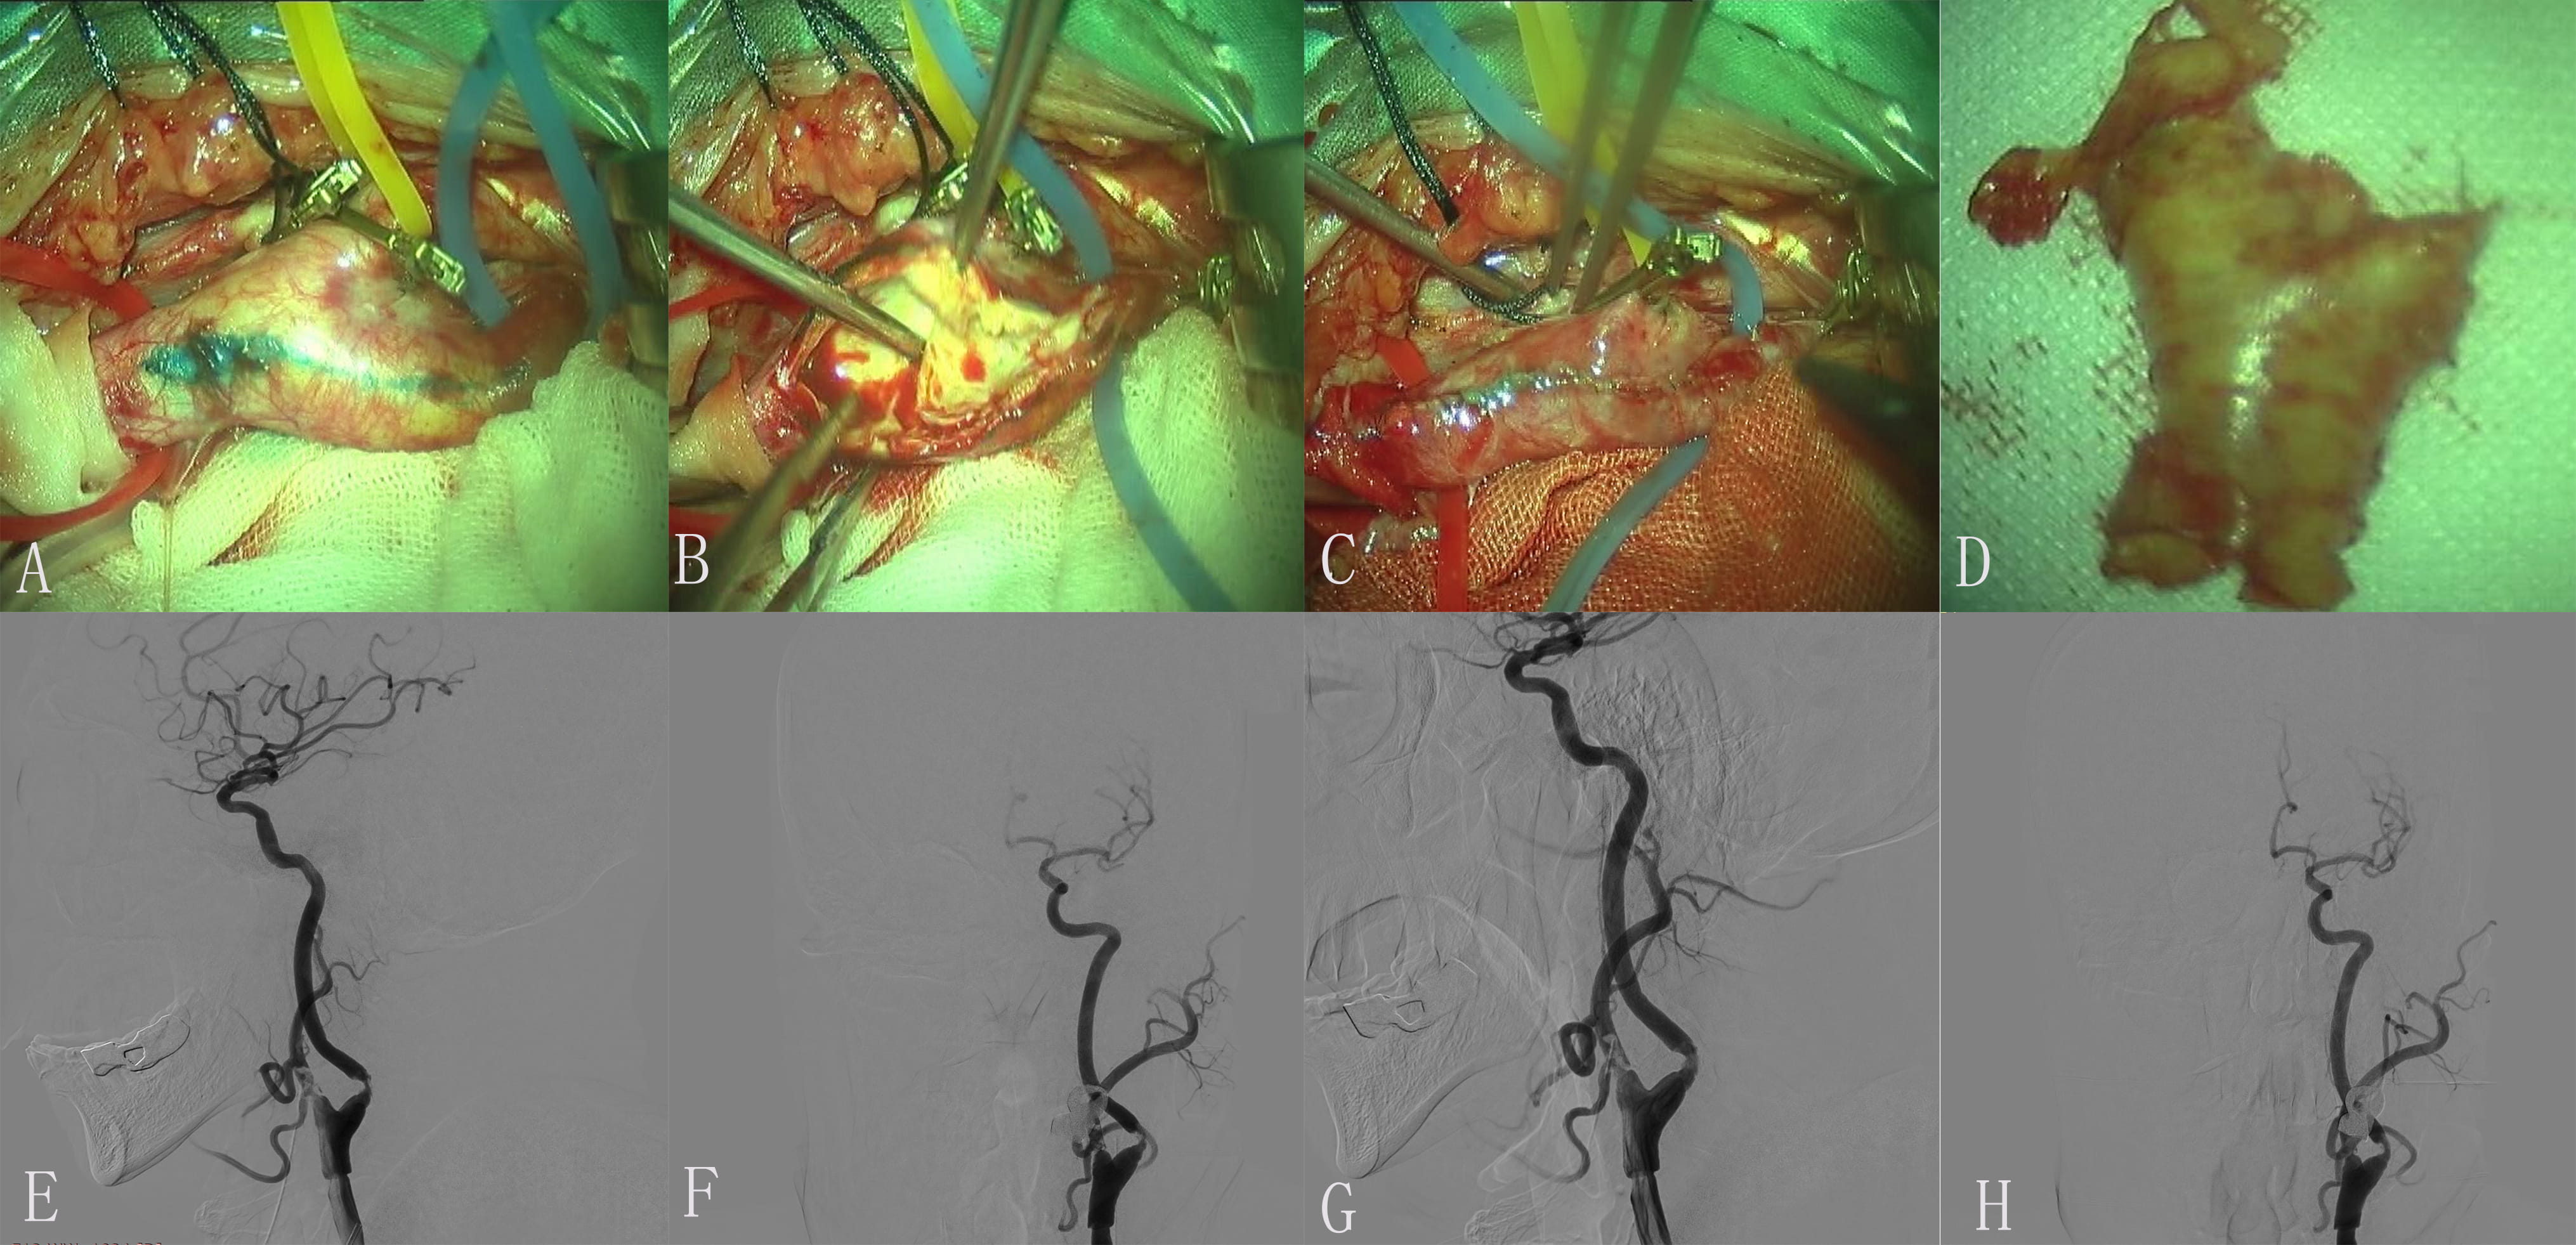

Under general anesthesia, the left CCA, ICA and ECA, STA were exposed. After the blockage of the artery, the anterior wall of the carotid artery is dissected. The plaque was presented as cloudy unstable, the intima of the ICA was carefully treated and fragments of the plaque were removed. Suturing the carotid artery with a continuous suture. Layer-by-layer suturing of the wound. The right lower limb was inhibited, and the femoral membrane was well fixed. The tension in the muscles of the limbs was normal. After the operation. The patient underwent a Computed Tomography (CT, Siemens, Forchheim, Germany) scan of the head, which ruled out intracerebral hemorrhage (ICH). DSA (Philips Medical Systems Nederland B.V., Eindhoven, Netherlands) has demonstrated that embolus forms during CEA (Fig. 2). Then, through the 6-French introducer sheath in the RFA and after the introduction of heparin (3000 U), the 6-French guide catheter (Cordis Corporation, Bridgewater, NJ, USA) was advanced into the proximal left CCA; the thrombotic plaque disappeared after the introduction of 0.5 mg of tirofiban (Grandpharma, Wuhan, China) into the artery. Postoperative arteriogram of the left ICA was found to be normal.

Fig. 2.Images of Case 2. (A,B) Preoperative left middle cerebral artery (MCA) and anterior cerebral artery (ACA) arteriogram revealed normal. (C,D) Preoperative left common carotid artery (CAA) arteriogram revealed a severe proximal internal carotid artery (ICA) stenosis. (E) Exposure of diseased vessel. (F) The endometrium of the CCA was dissected longitudinally and presented plaque. (G) Completed removal of plaque. (H) Incision suture. (I) Embolus was formed in carotid endarterectomy (CEA). (J) The thrombotic plaque disappeared after 0.5 mg tirofiban was administered to the artery. (K,L) Postoperative left ICA arteriogram revealed normal.